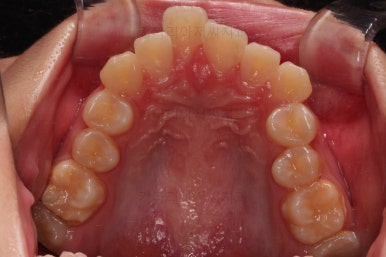

초진 시, 입 안의 모습입니다.

치아가 많이 삐뚤어요.

공간이 부족해서 앞니가 앞으로 많이 뻐드러졌고, 삐뚤한 양상 때문에 덧니가 되었네요.

어금니 맞물림도 좋지 못한 앵글씨 2급 부정교합 상태였어요.